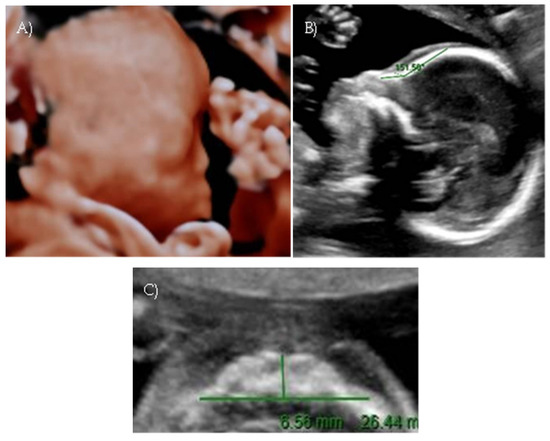

Polyhydramnios developed; a flat fetal facial profile with mild verticalization of the nasal bone (Nasal-frontal angle: 151.71°, cut-off: <143°) and slight prognathism were noted (Figure 4A–C).

Figure 4. Case 4. (A) Flat fetal profile. (B) 3D reconstruction of the facial profile. (C) Nasal-frontal angle: 151.71°.